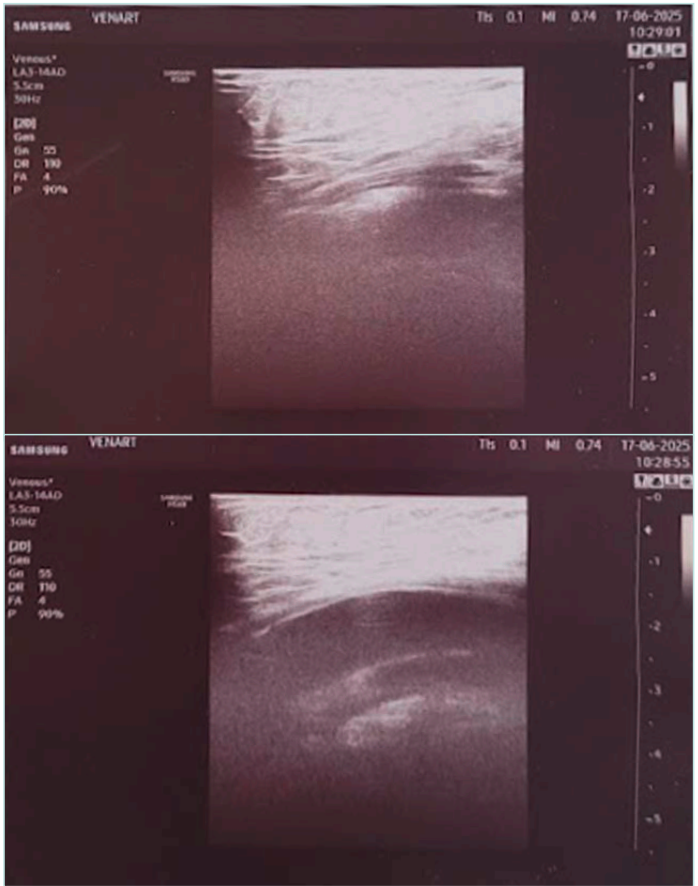

If there is no superficial venous insufficiency associated, in a supine patient, US can appear as normal (Figure 2).

Figure 2. Obese patient with normal non-dynamic venous duplex ultrasound and popliteal venous compression.